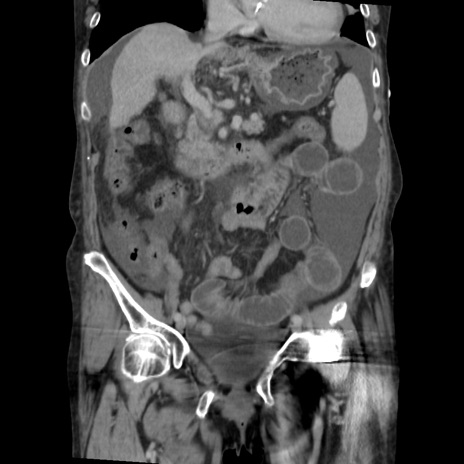

症例31(冠状断像)

【症例】80歳代 女性

【主訴】腹部膨満感

【現病歴】他院にて肝硬変にてフォロー中。1週間前から便秘、腹部膨満感、臍部腫瘤あり受診となる。

【既往歴】肝硬変